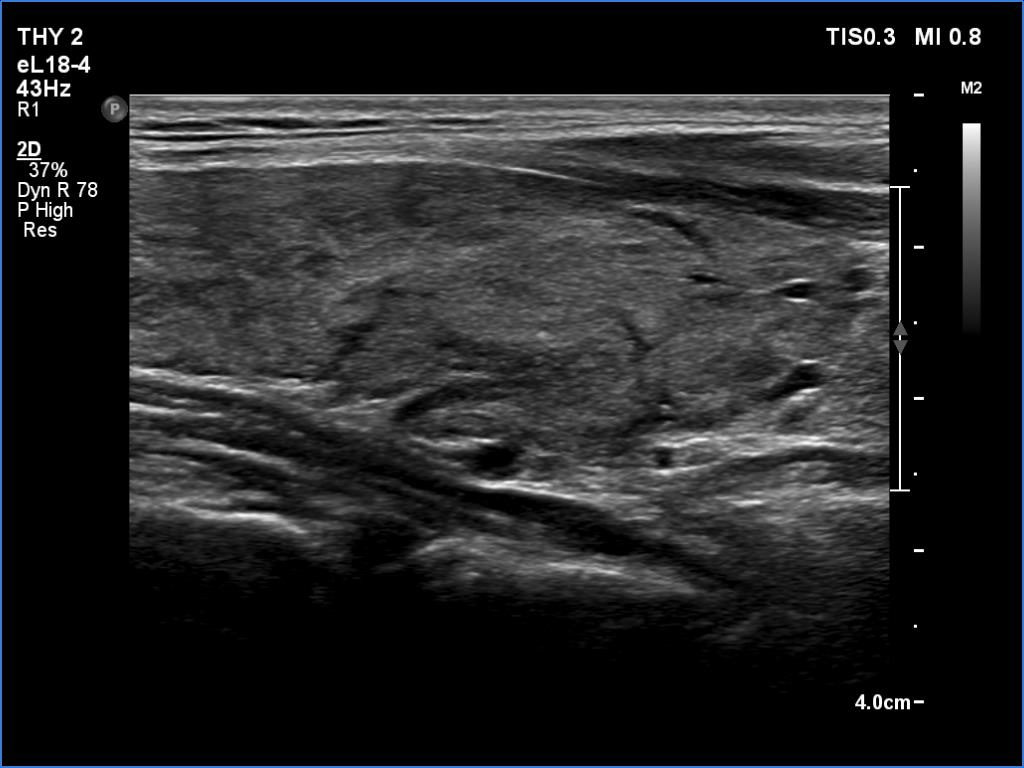

Graves' disease - case 121

Follow-up investigation 4 months after the initial one (ultrasonographic picture 7)

Lower part of the left lobe, longitudinal scan.